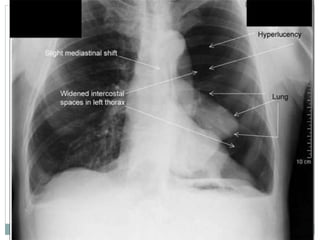

Pneumotórax